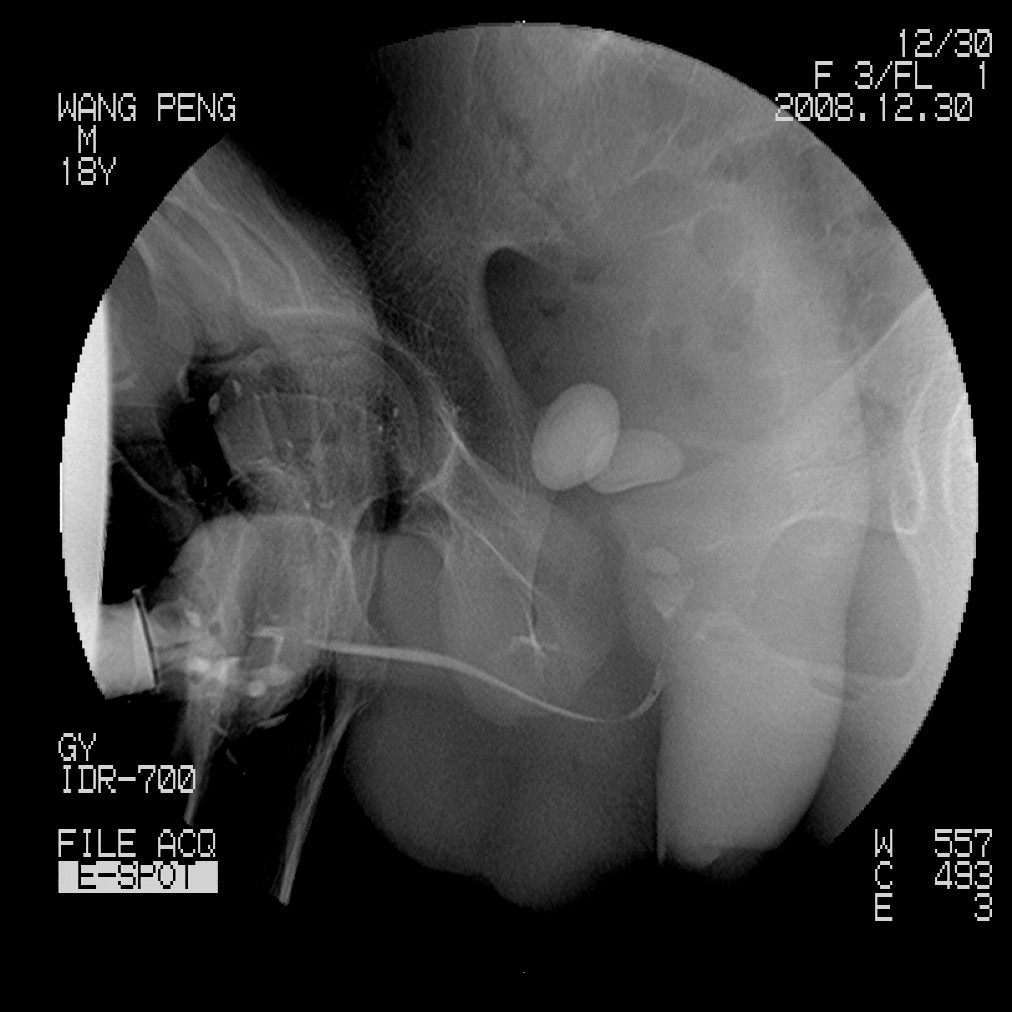

标题: X6910:经典的膀胱及尿道多发结石 [打印本页]

标题: X6910:经典的膀胱及尿道多发结石

患者,男,18岁,尿流不畅数月。

膀胱及后尿道多发结石,谢楼主分享

膀胱及尿道多发结石。

膀胱及后尿道多发结石,谢谢分享---------------------------